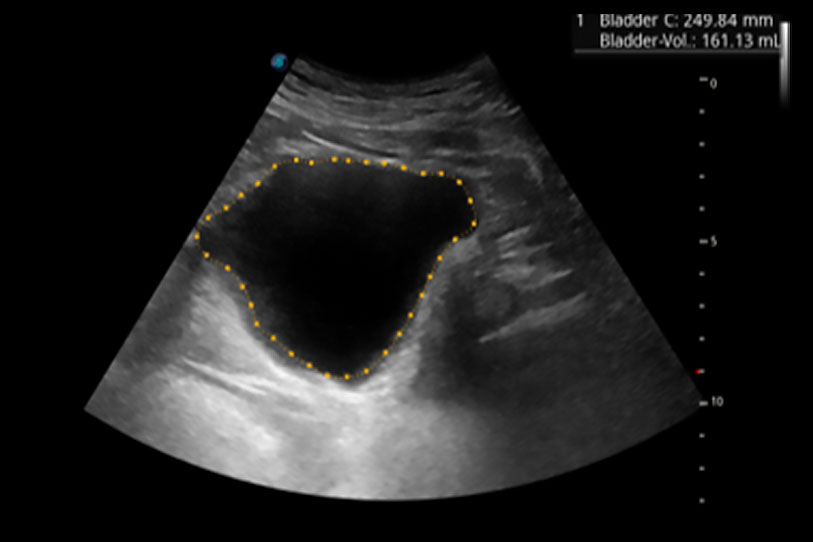

一鍵自動識別膀胱壁及自動測量膀胱容積,不受膀胱形狀和大小的限制,幫助醫(yī)生快速精準(zhǔn)獲得測量的數(shù)據(jù)。